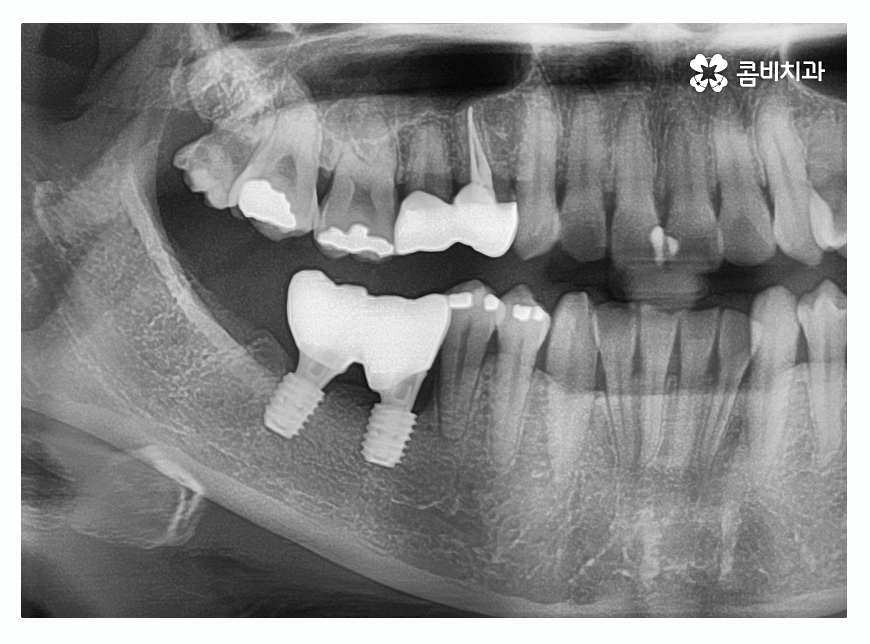

오늘 보시는 환자분의 경우에는 치주질환이 심해져서

여러 치아를 발치하게 된 사례로 자연치아의

수명을 다하지 못한 채 발치를 하는 것은 안타까운 일이지만

치주질환 관리를 제대로 하지 못할 경우에는

노년에 이르러 치아를 모두 상실하게 되는 경우도

많기 때문에 중년 이후에는 특히 주의할 필요가 있어요.

노년층의 경우에는 자연치아를 모두 잃거나 거의 다 잃게 되어

상악과 하악에 각각 8~10개 정도만 임플란트를 식립하여

브릿지 형태로 치아 보철물을 장착하는 전체임플란트 방식으로

치료를 진행하는 경우도 있어요.

중년 이후에는 당뇨나 고혈압 등의 전신질환이 있는 환자분들이

많이 찾아오시는데 임플란트를 건강하게 식립하고

치아의 기능을 회복하는 것도 중요한 부분이지만

임플란트는 재수술이 더 어렵고 고가의 시술인 만큼

수명을 오랫동안 잘 유지하기 위해 사후관리까지 철저할 필요가 있어요.